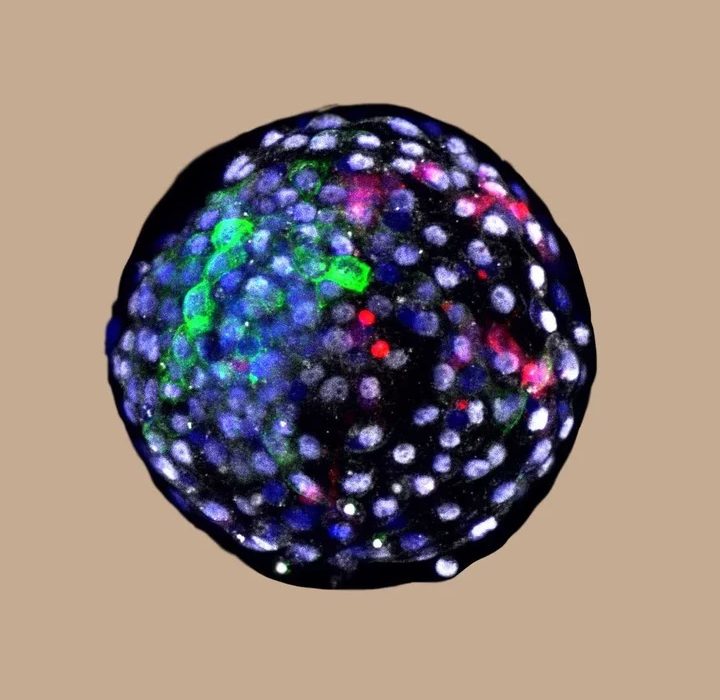

Inyectaron 25 células iPS (células madre pluripotentes inducidas de humanos) en embriones de monos macacos, cuya estructura genética está más relacionada con los humanos que las ovejas y los cerdos.

Después de una jornada, detectaron células humanas que crecían en 132 embriones y los estudiaron durante 19 días. Aprendieron cómo se comunican las células de ambas especies, lo que podría ayudar a encontrar alternativas para cultivar órganos para trasplantes en otros animales.